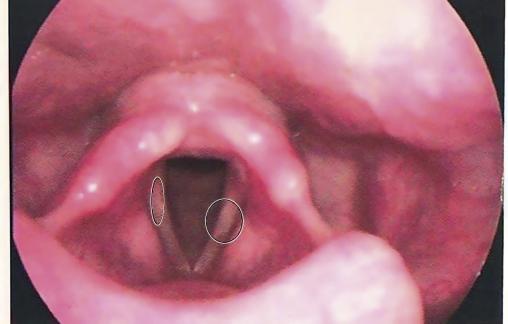

Les nodules, visibles en fibroscopie, sont blanchâtres, bilatéraux et symétriques, arrondis ou spiculés, situés en miroir sur les cordes vocales.